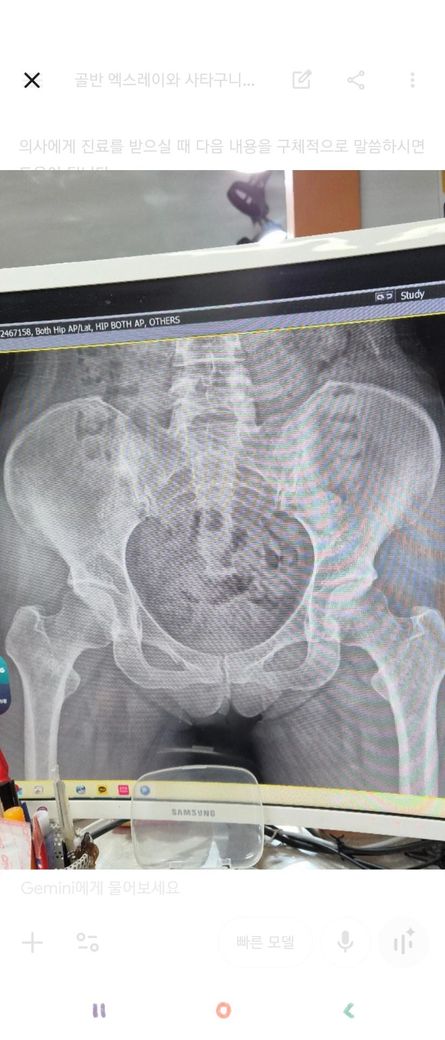

고관절 영상인데 한번만 봐주세요!!

가동범위 제한이 있어 엠알아이를 찍었는데..

문제될만한게 있을까요?

윤활막액염?인가 그렇다는데

• 1번 째 사진